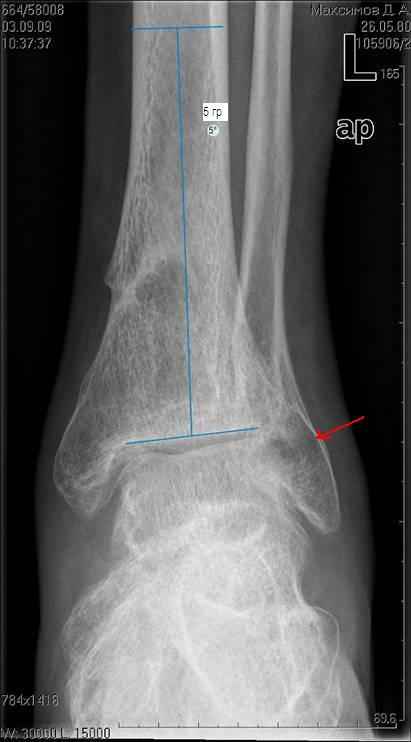

Здравствуйте коллеги. Представляю молодого человека 28 лет, получившего травму в апреле 2008года. Травму он получил на работе, левая голень со стопой оказались зажатыми между двумя тяжелыми предметами. В результате открытые переломы 1,2,3 плюсневых костей с размозжением мягких тканей над ними, открытый перелом наружной лодыжки со смещением дистального отломка кзади и подвывихом стопы кнаружи с размозжением мягких тканей над лодыжкой, закрытые переломы внутренней лодыжки и дистального метэпифиза большеберцовой кости.Учитывая наличие размозжения тканей стопы и области голеностопного сустава лечили в аппарате внешней фиксации. Переломы срослись, однако имеет место незначительный подвывих стопы кнаруже и неправильно сросшийся отломок наржной лодыжки (смещен кзади)Сегодня пациента ничего не беспокоит (с его слов. Клинически левый голеностопный сустав не отечный,пальпация всех структур данного сустава безболезненна. Имеет место ограничение тыльного сгибания стопы (сгибание к тылу стопы составляет до 10-15 гр), в связи с этим имеет место гиперподвижность в суставе Шопара. Пациент ходит со стельками (индивидуальные).Нужна ли пациенту реконструктивная операция в голеностопном суставе: исправление взаимоотношений в наружных отделах голеностопного сустава или что еще?С уважением Батал Шушания.

Наверное наружная лодыжка ушла назад не одна - такое впечатление, что был сломан и задний отдел б/берцовой кости (малоберцовая вроде прямая, а эпифиз широковат, как-то). Поэтому, думается, что гоняться за лодыжкой и синдесмозом не стоит. А вот вальгусный голеностоп и деф. артроз таранно-ладьевидного сустава - налицо. Вальгус надо устранять и, скорее всего, в АВФ единым блоком (надлодыжечная остеотомия обеих костей). Что пациент сам-то хочет? Если его устраивает нынешнее положение вещей, в стельках ему комфортно, то зачем огород городить (к этому суставу, рано или поздно, все-равно придется возвращаться)?

учитывая асептический некроз блока тарана - артродез.

кисты тарана прослеживаются хорошо.

На рентгенограмме вальгус, на боковом снимке не видна суставная щель и клинически явная деформация.